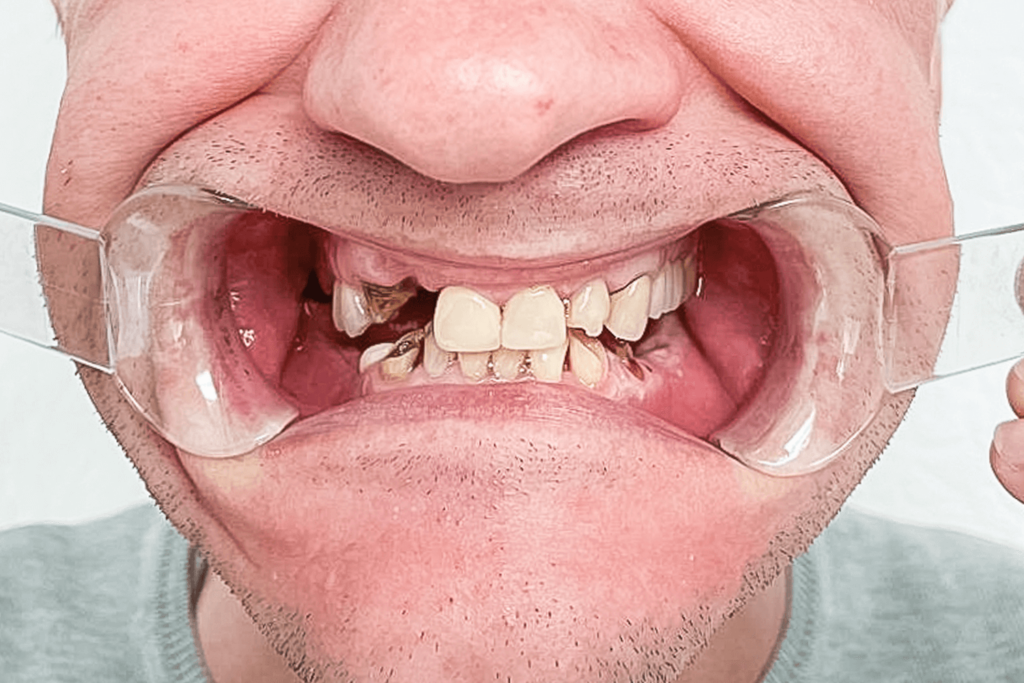

К нам в клинику обратился пациент с жалобой на перелом верхнего второго зуба справа. Кроме того, пациента очень беспокоила сама причина перелома, ведь он не понимал, как такое могло произойти.

При осмотре пациента было обнаружено отсутствие восьми зубов: 5, 6, 7, 8 с правой и левой сторон на нижней челюсти. Нижние фронтальные зубы были поражены в результате патологического стирания вызванного массивной антагонистической конструкцией (металлокерамические коронки) на фронтальных зубах верхней челюсти. После 3D КТ-диагностики, осмотра и выслушав пожелания пациента, предложили следующий план лечения: